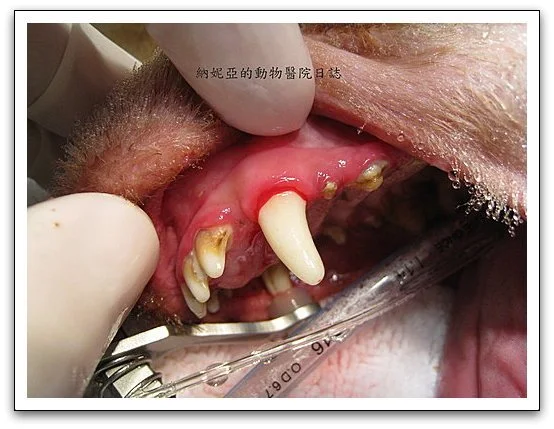

大家可以清楚看到這隻狗狗的牙齒狀況,以及牙結石的累積程度。